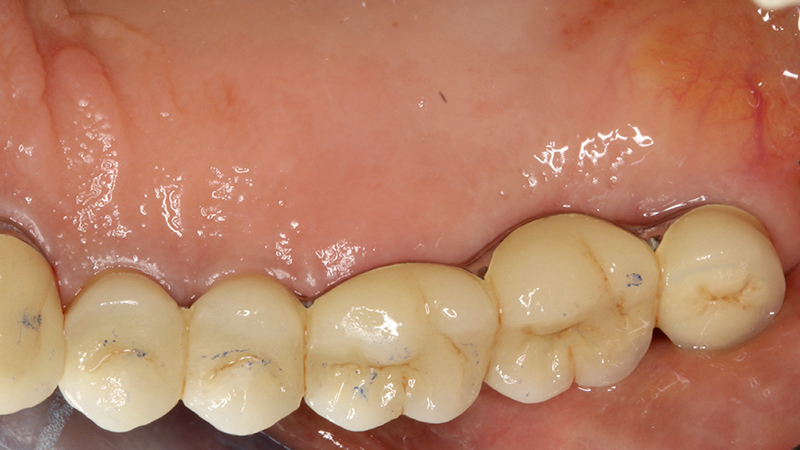

La finalizzazione del caso avveniva con protesi in metallo-ceramica passivata su cappe conometriche in bocca (Figs. 24, 25, 26, 27, 28, 29, 30, 31, 32) e radiografie finali ad un anno dal carico (Figs. 33, 34).

Applicazione ponte 17-14 in metallo ceramica su cappette conometriche passivate in bocca mediante cemento

Fig. 24 - Applicazione ponte in metallo ceramica su cappette conometriche passivate in bocca mediante cemento Multilink Hybrid e risultato finale

Applicazione ponte 17 - 14 in metallo ceramica su cappette conometriche passivate in bocca mediante cemento Multilink Hybrid e risultato finale

Fig. 25 - Applicazione ponte 17 - 14 in metallo ceramica su cappette conometriche passivate in bocca mediante cemento Multilink Hybrid e risultato finale

Fig. 26 - Applicazione ponte 17 - 14 in metallo ceramica su cappette conometriche passivate in bocca mediante cemento Multilink Hybrid e risultato finale

Fig. 27 - Applicazione ponte 17 - 14 in metallo ceramica su cappette conometriche passivate in bocca mediante cemento Multilink Hybrid e risultato finale

Fig. 28 - Applicazione ponte 17 - 14 in metallo ceramica su cappette conometriche passivate in bocca mediante cemento Multilink Hybrid e risultato finale

Fig. 29 - Applicazione ponte 17 - 14 in metallo ceramica su cappette conometriche passivate in bocca mediante cemento Multilink Hybrid e risultato finale

Fig. 30 - Applicazione ponte 17 - 14 in metallo ceramica su cappette conometriche passivate in bocca mediante cemento Multilink Hybrid e risultato finale

Fig. 31 - Applicazione ponte 17 - 14 in metallo ceramica su cappette conometriche passivate in bocca mediante cemento Multilink Hybrid e risultato finale